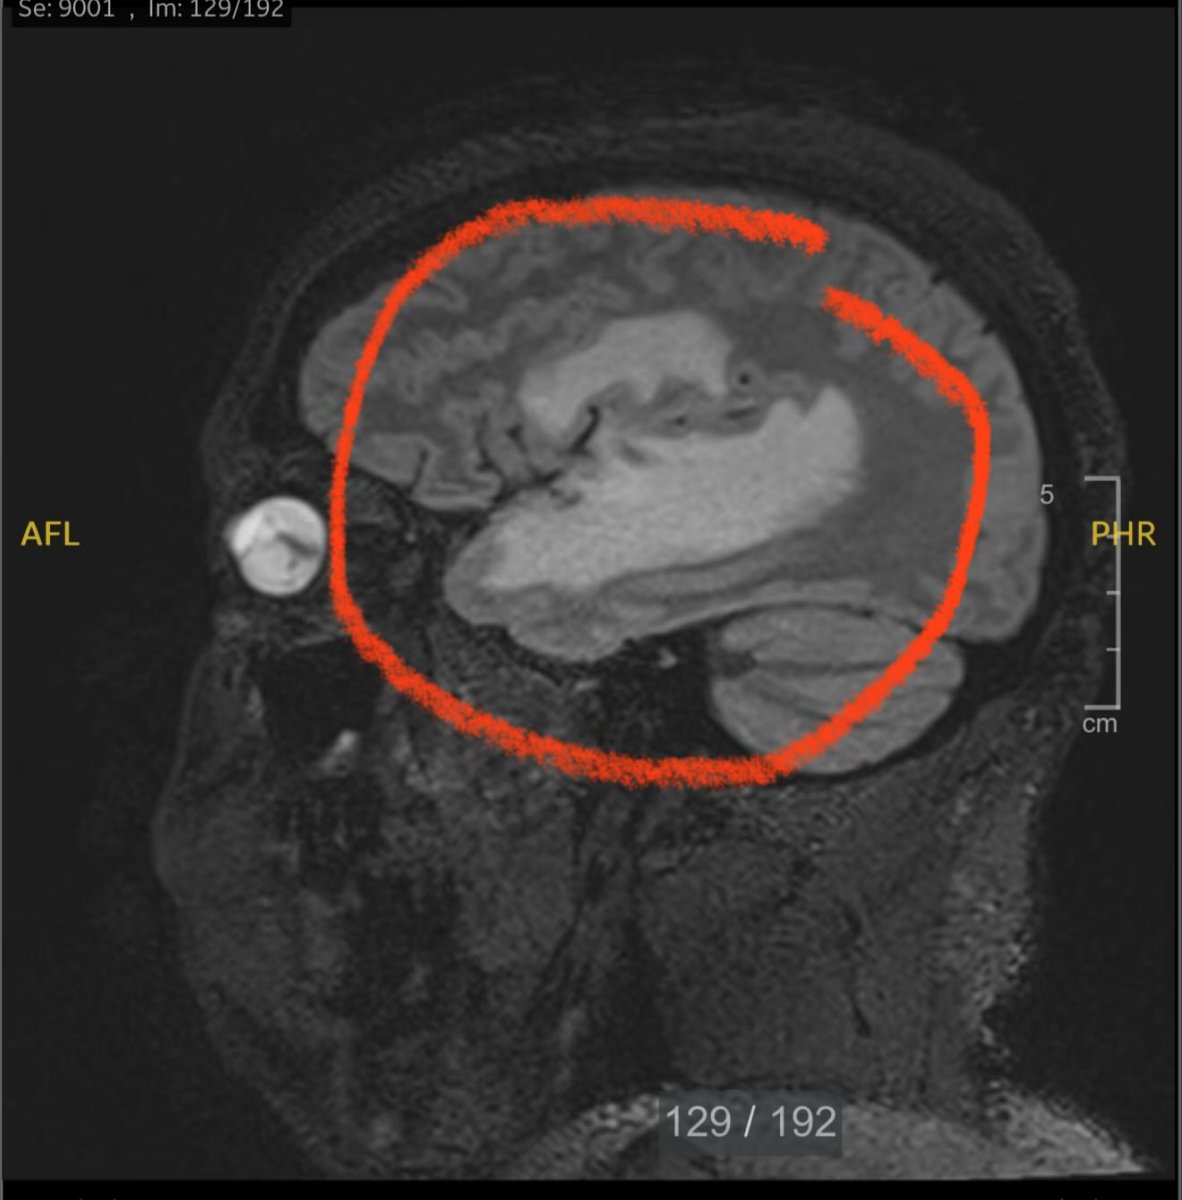

Nate The Lawyer (@NatetheLawyer) ~ Here is my brain tumor. Surgery had to be postponed because it’s massive. Will be under the knife Wednesday.